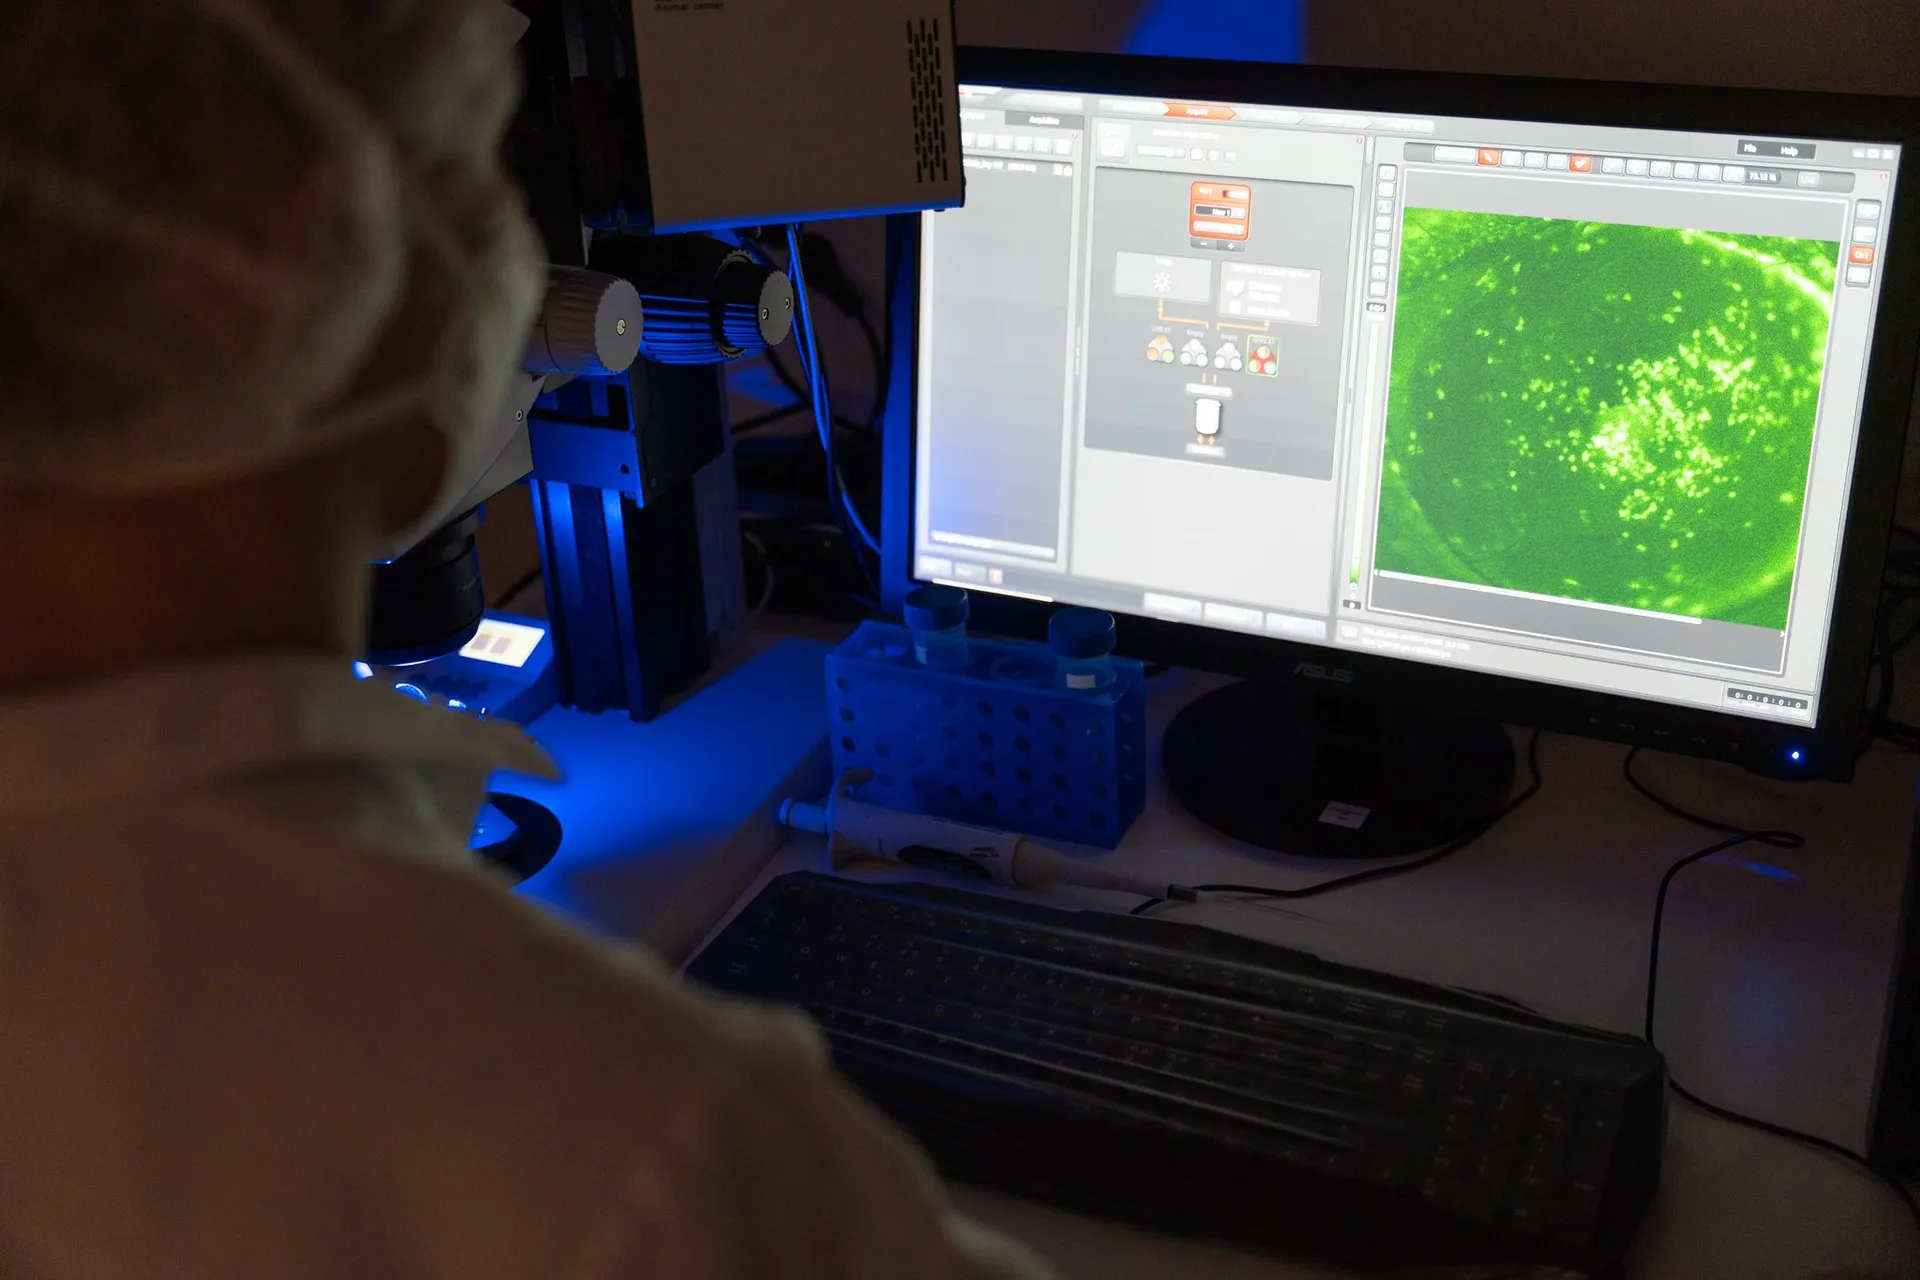

We offer comprehensive, non-invasive in vivo assessments including corneal fluorescein staining imaging, rose bengal staining imaging, and tear volume measurements. Additionally, we provide detailed histological analysis of lacrimal gland inflammation, corneal epithelial thickness and conjunctival goblet cell density.

– Grading of corneal epithelial damage (corneal fluorescein staining and rose bengal staining)